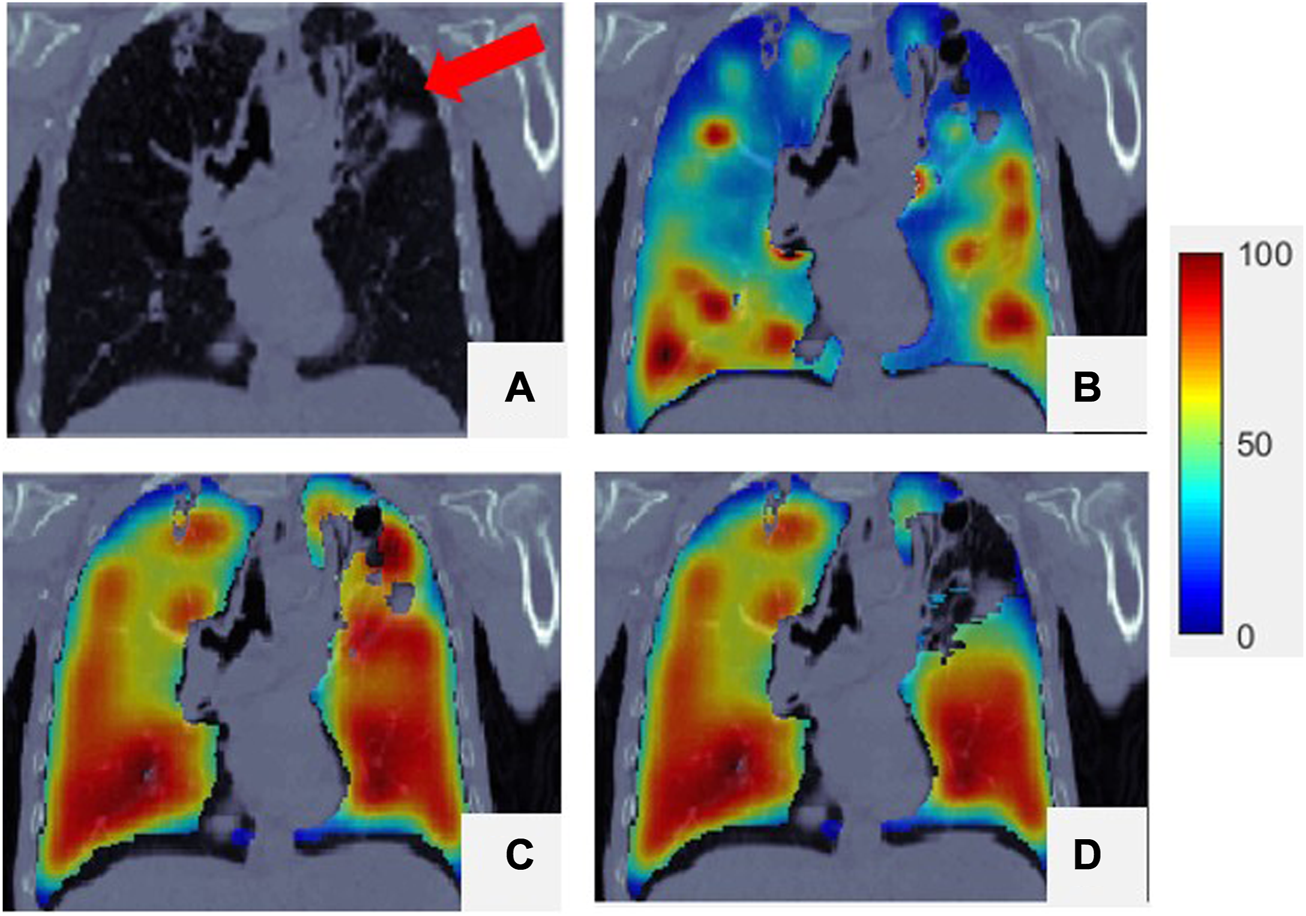

The correlation between the Dmean from CT and the Ventmean for the super-voxel volume from SPECT was 0.59 ± 0.09, indicating that super-voxels with a lower mean density tend to have a lower function value than super-voxels with a higher mean density. This moderate-to-strong correlation means that the Dmean of a super-voxel can be used as a surrogate for Ventmean when generating , as mentioned in Section 2.5. Figure 4 presents a comparison of SPECT with . The low-functioning lung region, indicated by the red arrow in the CT image and by the blue and black-blue area in the ventilation image (Figure 4B), can be identified using (dark blue area in Figure 4D). The mean correlation coefficient between and SPECT was 0.62 (range: 0.37–0.77). The mean correlation coefficients of SPECT with CTex, ; ; ,; were 0.16 ± 0.16, 0.33 ± 0.14, 0.23 ± 0.10, 0.39 ± 0.18, and 0.33 ± 0.15 respectively. These results indicate that is closer to SPECT than conventional DIR-based methods. The super-voxel based method can improve the correlations of the DIR-based CTVIs by 0.06 and 0.10 for ; , respectively. A similar improvement was also reported by Szmul’s study (Szmul et al., 2019).

The mean DSC values of the high-functioning () and low-functioning regions () on images were 0.63 ± 0.07 and 0.81 ± 0.03, respectively. Because the criterion for dividing the lung is the 66th, the low-functioning region is larger than the high-functioning region, and is higher than . As shown in Figure 4, the locations of the low-functioning regions on the images matched those on the SPECT images, but the highest-functioning regions (dark red area) just exhibited a certain amount of overlap. The mean values of , , , and were 0.43 ± 0.08 and 0.42 ± 0.05, 0.49 ± 0.11, and 0.48 ± 0.07, respectively, and the corresponding mean values were 0.70 ± 0.04, 0.70 ± 0.03, 0.74 ± 0.06, and 0.73 ± 0.04, respectively.

For some patients, yielded low correlation with SPECT. However, this could be improved. As indicated by the red arrow in Figure 5A, a defective lung region with a high density at the top of the left lung caused a falsely high ventilation value, as shown in Figure 5C. Such errors can be corrected by manually contouring the defect regions via assignment to a low ventilation value. In this case, the final correlation coefficient increased to 0.52, as shown in Figure 5D.

FIGURE 5

Comparison of SPECT image and images for a representative case. (A) Is CT; (B) is the SPECT of the lung region superimposed onto the CT; (C) is the origin of the lung region superimposed onto the CT; (D) is the corrected of the lung region superimposed onto the CT. For all the figures, their 99th percentile and higher values were scaled to 100, and the minimum value was scaled to 0.